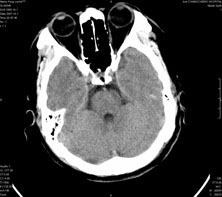

男,41岁,间断抽搐1小时,失神5分钟,bp130/90mmhg。低密度区ct值约16hu。

脑实质见多发散在的钙化点,左顶叶见一囊变灶,多考虑脑囊虫。

脑囊虫,部分囊内见头节。

脑实质见多发散在的钙化点,右颞、顶叶见囊性灶,考虑脑囊虫。